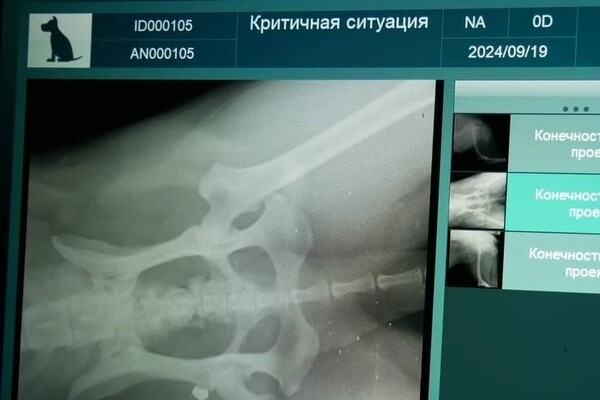

«Она скулила от боли, бежала через весь парк, истекая кровью, а потом еще долго тряслась от страха и шока. Глубокое проникновение в заднее бедро. Скорее всего, кусок холодного металла навсегда останется в теле этого умного доброго животного. Надеемся, что заражения и дальнейших осложнений удастся избежать. Лечение начато», – говорится в сообщении зоозащитницы.

Оплатить рентген и ветеринарные препараты для лечения раненого животного помогли неравнодушные. Заявление в полицию написали в тот же день. Комментариев по поводу этого инцидента правоохранители пока не предоставляли.